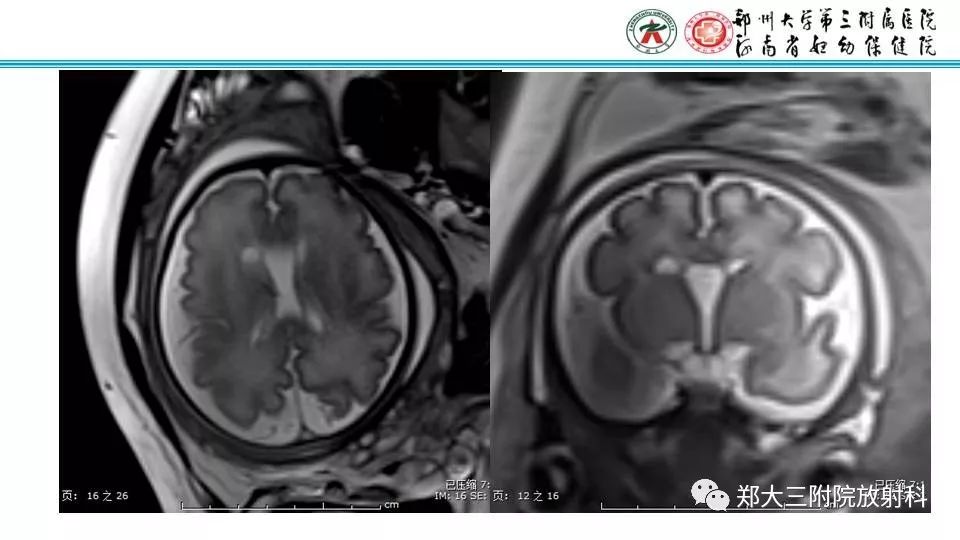

【PPT】室周假性囊肿-1